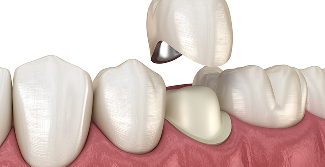

STEP 04

신경치료04

치아파절 방지를 위한

크라운 보철 씌우기

골드 크라운

치아와의 적합성이 뛰어나며, 씹는 힘이 강한 어금니에 적합합니다.

금속 재료이지만 생체 친화적이며, 잇몸 자극이 적습니다.

• 높은 강도

• 생체 친화적